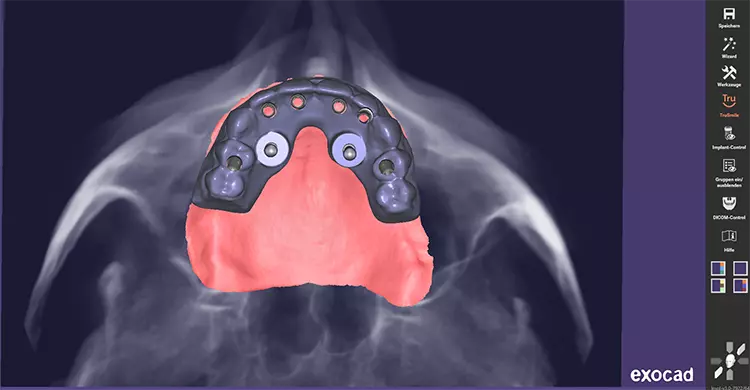

Hierzu wurde eine digitale Planung des Zahnersatzes im Sinne eines Backward Planning erstellt (Abbildung 3 und 4). Nachdem eine digitale Volumentomographie (DVT) des Patienten mit dem vorhandenen Zahnersatz in Okklusion inklusive Referenzpunkten und zusätzlich eine DVT der Prothese extraoral durchgeführt wurde, konnten im Anschluss mit dem Programm Exoplan® beide Scans gematcht werden. Auf dieser Grundlage wurden die sechs Implantate virtuell in idealer Position unter Berücksichtigung des ortsständigen Knochens geplant.

Die Vermeidung einer Sinusbodenelevation, sowie ein maximal großes Unterstützungspolygon standen im Fokus der präoperativen Planung für die festsitzende prothetische Versorgung. Dabei ergab sich ein 17 bzw. 30 Grad Neigungswinkel der distalen Implantate, der durch die Mesostruktur der Multi-unit Abutments ausgeglichen werden sollte, um eine gemeinsame Einschubrichtung für die geplante provisorische Brückenversorgung zu ermöglichen.

Das schon präoperativ erstellte Brückenprovisorium wurde mit großzügigen Aussparungen in regio der Sekundärstrukturen erstellt, um intraoperative Abweichungen von der Planung ausgleichen zu können. Für den OP-Situs resultierte daraus folglich eine navigierte Führungsschablone (fully-guided) und ein laborgefertigtes Sofor tversorgungsprovisorium (Abbildung 5). Am Tag der Operation erhielt der Patient präoperativ eine Single-shot-Antibiose.